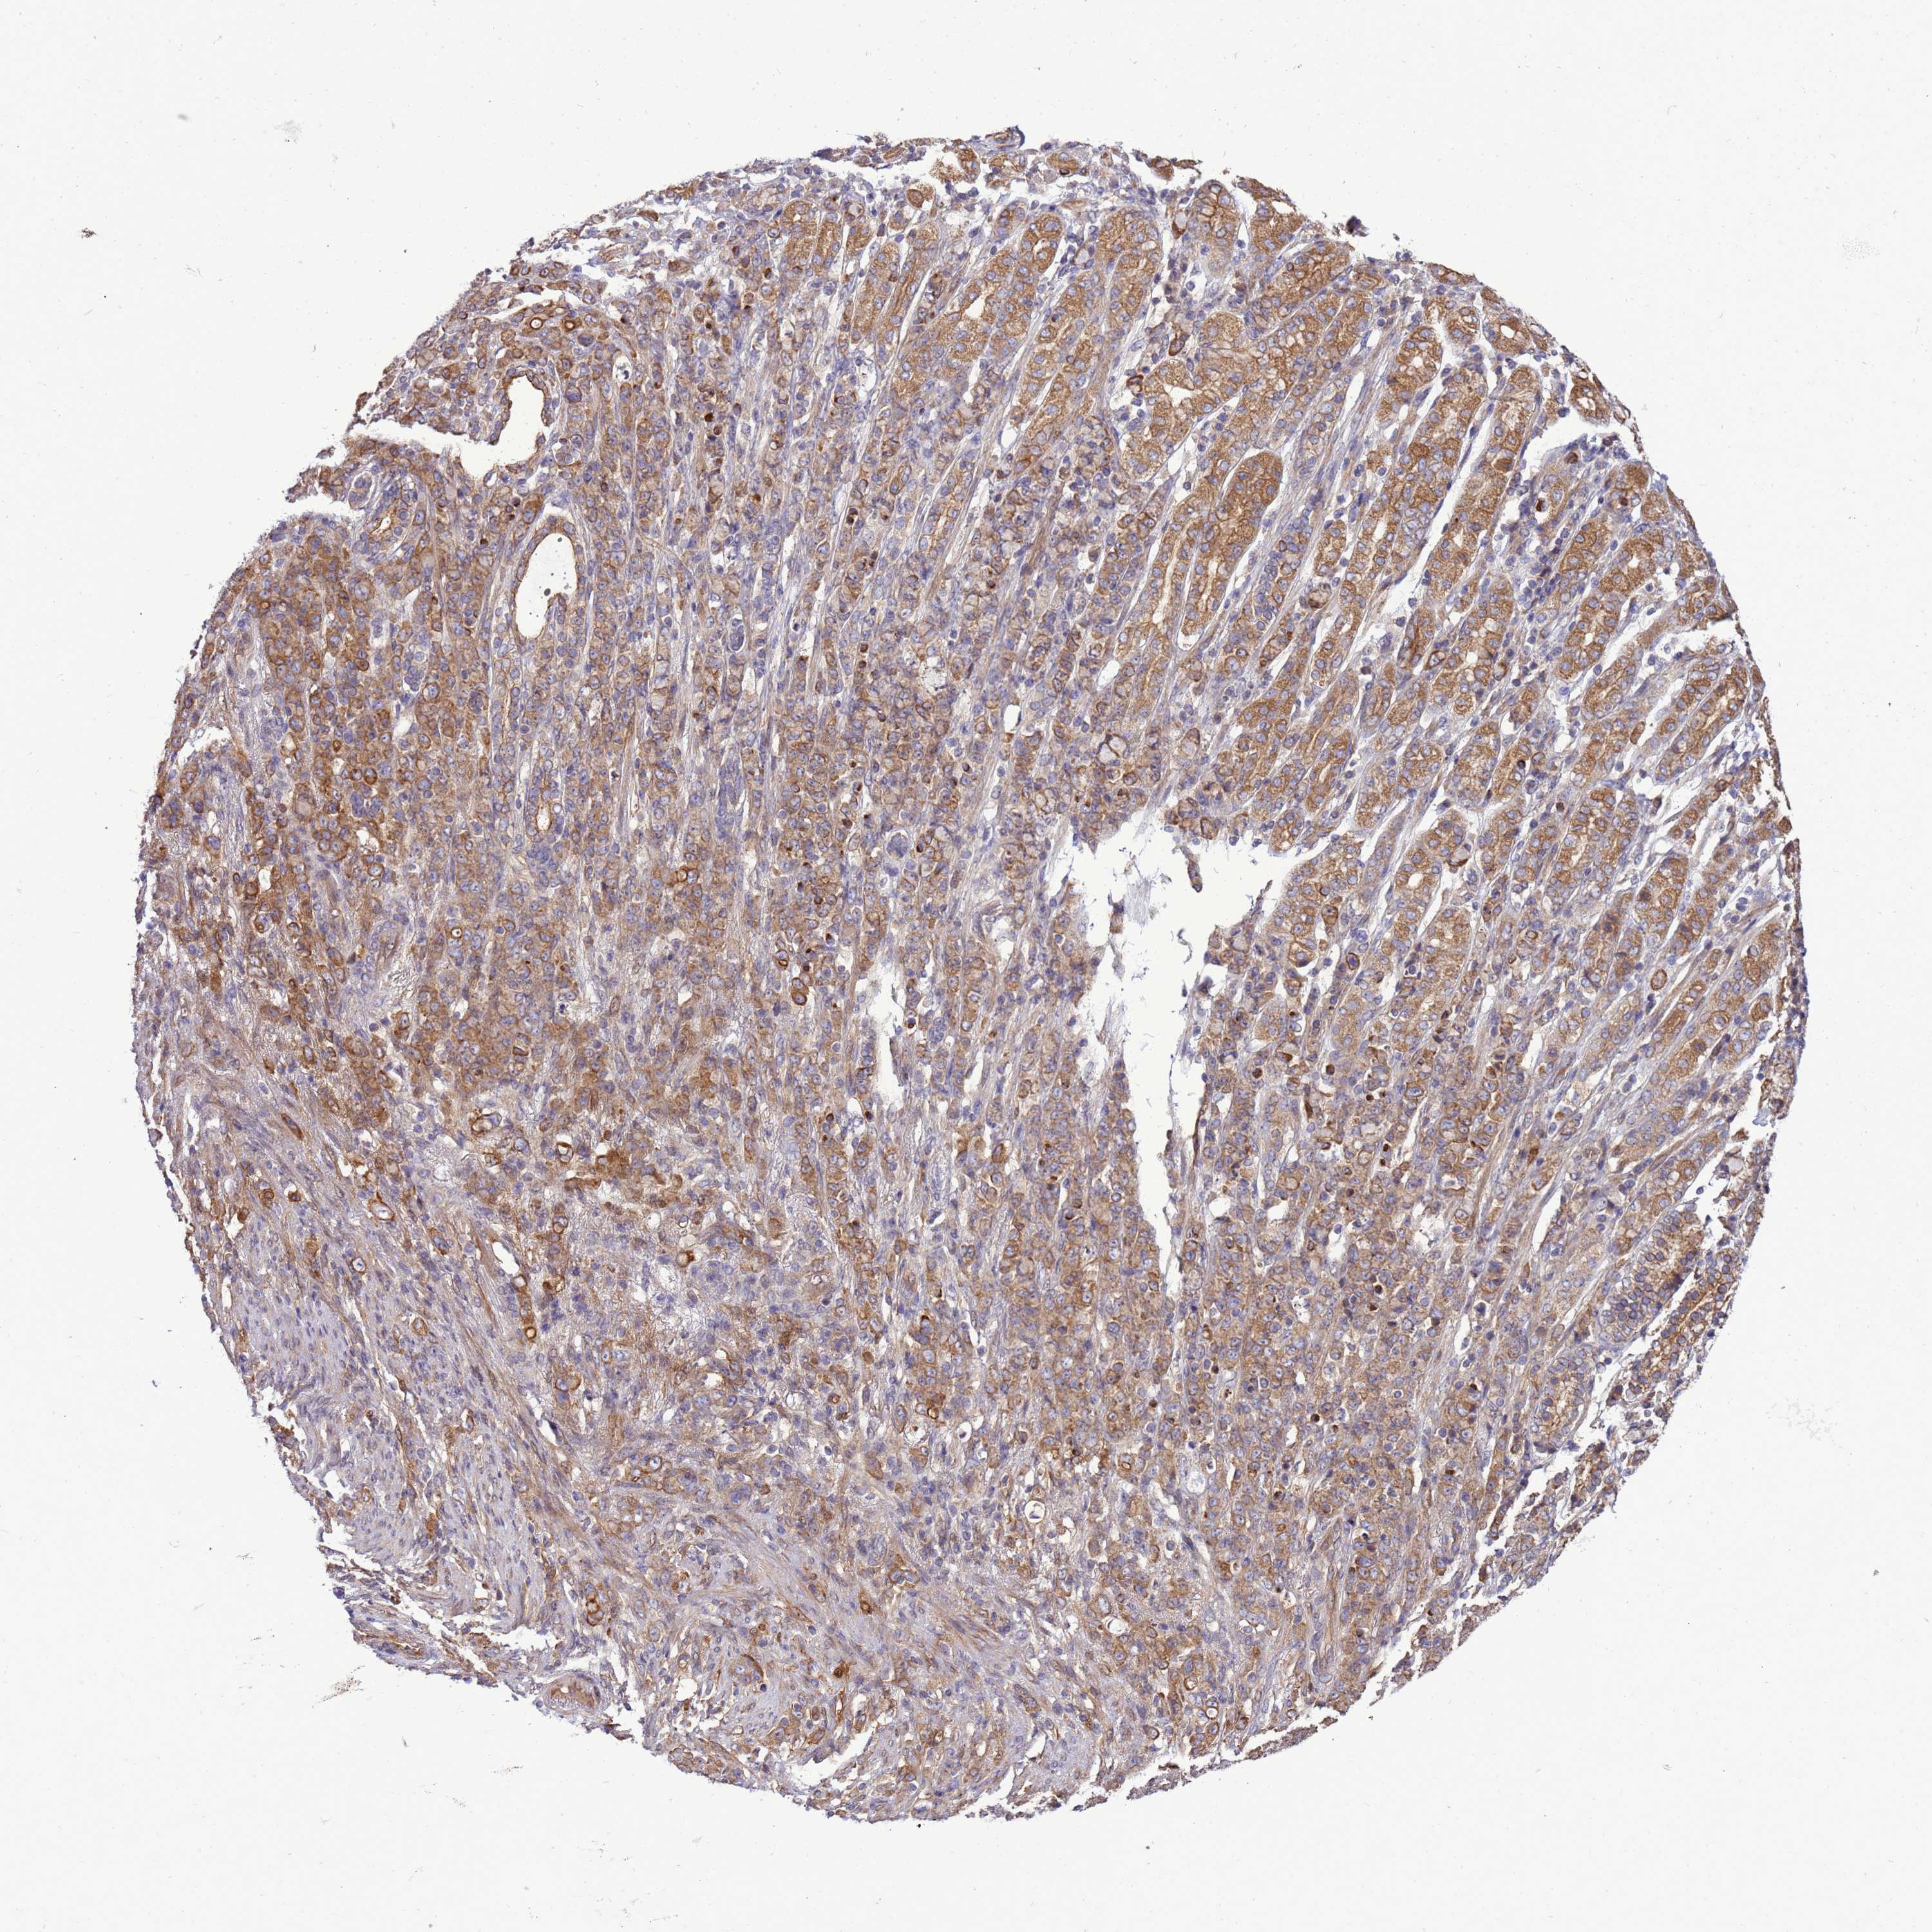

STOMACH CANCER - Protein expressioni

A mouse-over function shows sample information and annotation data. Click on an image to view it in a full screen mode. Samples can be filtered based on level of antibody staining by selecting one or several of the following categories: high, medium, low and not detected. The assay and annotation is described here.

Antibody stainingi

Antibody staining in the annotated cell types in the current human tissue is reported as not detected, low, medium, or high, based on conventional immunohistochemistry profiling in selected tissues. This score is based on the combination of the staining intensity and fraction of stained cells.

Each image is clickable and will lead to virtual microscopy that enables deeper exploration of all samples and also displays staining intensity scores, fraction scores and subcellular localization as well as patient and tissue information for each sample.

Antibody HPA040574

Antibody HPA047804

Staining

High

Medium

Low

Not detected

Intensity

Strong

Moderate

Weak

Negative

Quantity

>75%

75%-25%

<25%

None

Location

Nuclear

Cytoplasmic/membranous

Cytoplasmic/membranous,nuclear

Adenocarcinoma, NOS

Adenocarcinoma, High grade